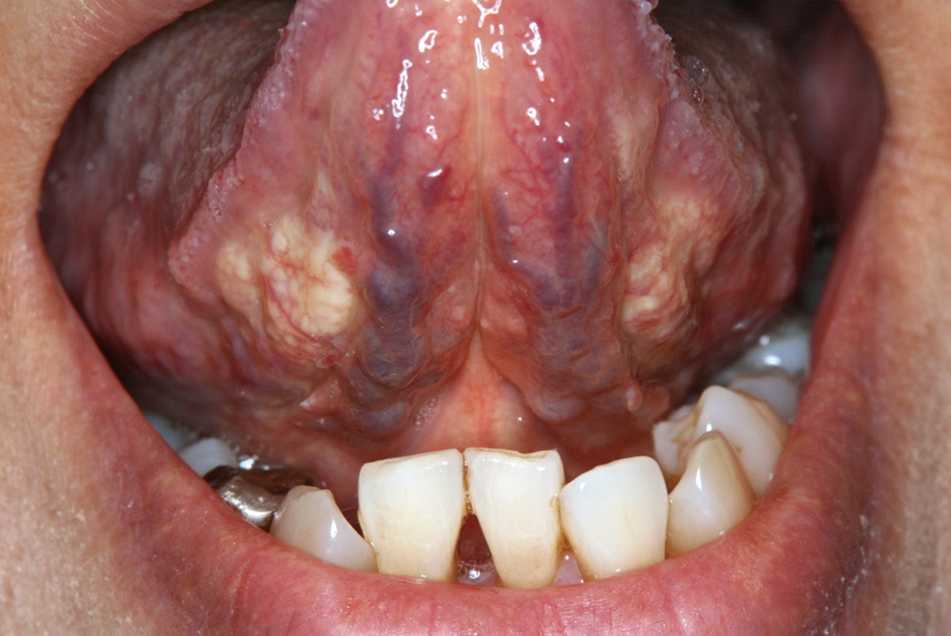

口腔内所見:両側舌下面にほぼ対称性に黄白色不整形な弾性やや硬の腫瘤を認めた(図1)。

今回は2025年12月号より、「両側舌下面の黄白色腫瘤」についてです。